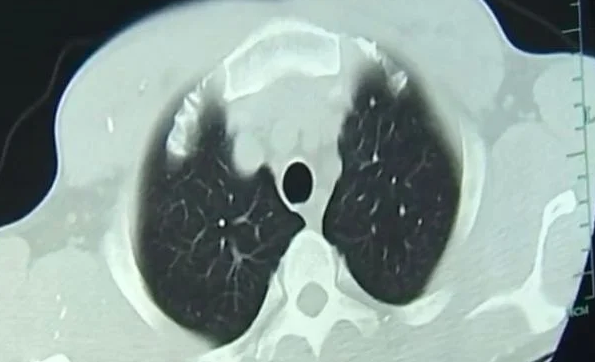

Only one month after he consumed the undercooked pork, doctors quickly identified the cause of Zhongfa’s seizures and fainting episodes. His body was utterly infected with tapeworms. These unwelcome guests had made themselves at home in his brain, lungs, and other parts of his body. The worm larvae had spread throughout his body via his bloodstream.